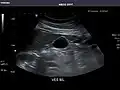

Kidneys: Right and left kidneys measure 11.5 cm and 12 cm in length respectively. No hydronephrosis. Small left lower pole kidney cyst.

Right kidney -